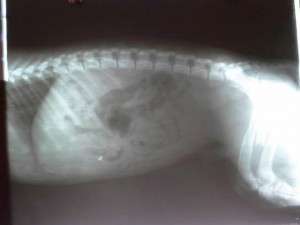

He was living his life in a market, where people threw him a bit of bread at times. At night, he took shelter under the market stands, or under a car parked in the market place. Yet, everything turned into a nightmare, when a car backed up and the poor dog couldn’t get out of the way. He was left there unable to move, while the heartless person who hit him abandoned him and went on with his life. A desperate call from a lady who worked at the market drew our attention, and we could not ignore the situation, although we are swamped with animals and problems of all kinds. The little dog’s first surgery was successful, and now he is at the clinic, where he will have to undergo more surgery. We hope that in the end he will walk again.

Hit by a car